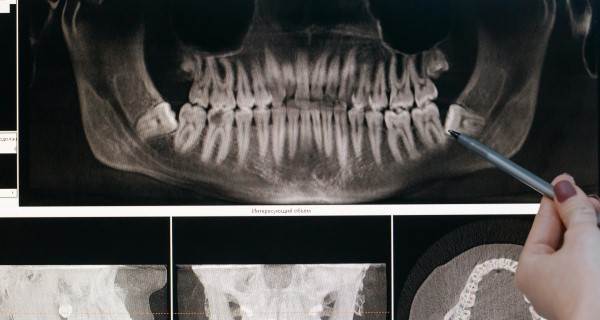

Periapikal röntgen, dişlerin kök yapılarını ve çevresindeki kemik dokularını detaylı bir şekilde gösterebilir. Bu sayede, diş hekimleri çürümüş dişleri, kök enfeksiyonlarını veya çene kemiğinde oluşan sorunları tespit edebilir. Çekilen röntgenler genellikle siyah-beyazdır ve dişlerin durumu hakkında net bir fikir sunar.

Panoramik Röntgen: Panoramik röntgen, çenenin tüm dişlerini ve çevresindeki yapıları tek bir görüntüde gösteren daha geniş bir röntgen türüdür. Ancak bireysel dişlerin kök yapısına dair detaylı bilgi vermez.

Koni Beams Röntgen (CBCT): Bu daha gelişmiş bir teknik, üç boyutlu görüntüler elde edilmesine olanak tanır. Özellikle implant uygulamaları ve ortodontik tedaviler öncesinde detaylı bilgi sunar. Ancak, daha yüksek düzeyde radyasyona maruz kalmayı gerektirebilir.